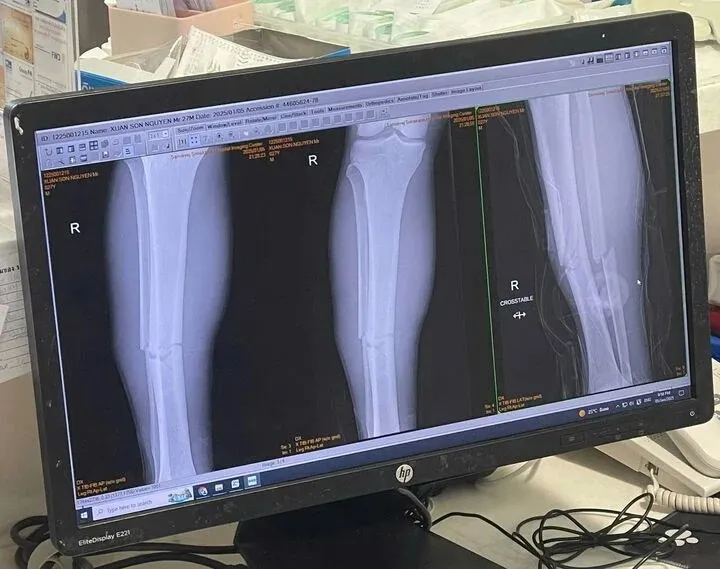

xuan-son-7-23412467.jpg

Đây mới chính là kết quả chụp phim của Xuân Son chụp lại máy tính bệnh viện

Trường hợp của Nguyễn Xuân Son theo các bác sĩ thì nếu không có các tổn thương khác như dây chằng khớp gối mà chỉ là gãy xương chày và xương mác thôi thì sau khi giải phẫu cố định xương đúng vị trí sẽ kết hợp giữa hồi phục và tập luyện thì mất từ 6 tháng đến 1 năm có thể thi đấu bình thường trở lại.